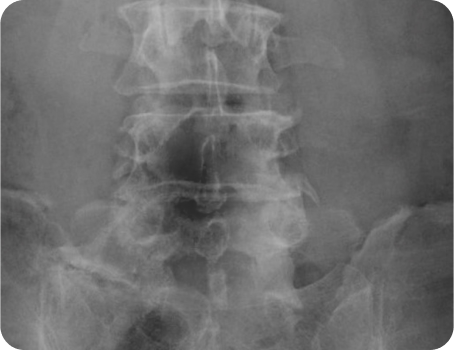

이제는 하세요!

엑스레이 검사

CT 검사

MRI 검사

족압 분석 검사

모아레 근육 균형 검사

적외선 체열 검사

다리 길이 검사

체성분 검사